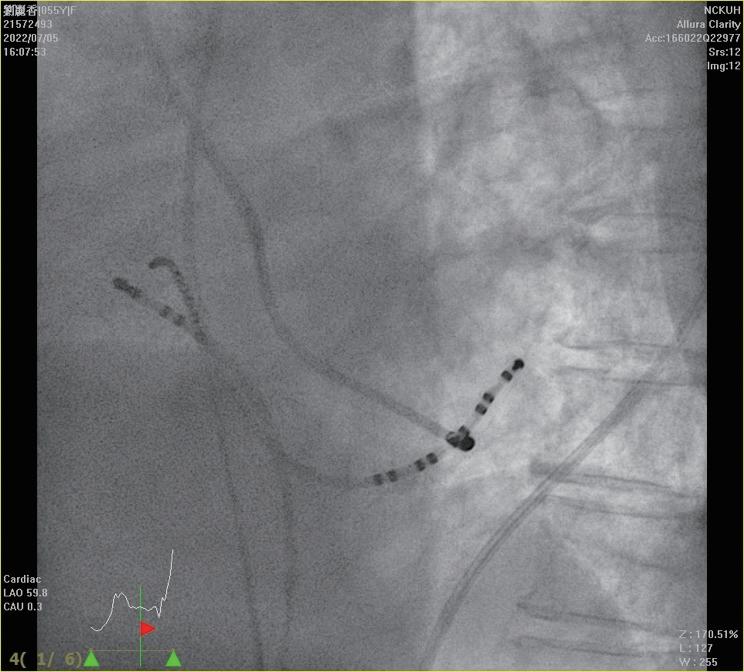

中華民國心律醫學會‧ Taiwan Heart Rhythm Soclety ‧中華民國 111 年 9 月出刊 我們在此報告一個來進行 PSVT 電燒的 55 歲 女性,沒有其他慢性病症,甲狀腺檢查正常,因為 PSVT 前往急診,發作時十二導程心電圖如下 ( 圖一 ) , 看起來是 short-RP 的 tachycardia 並且有 electrical alternans 的現象,第 12 個波組看起來比較不一樣,推測有可能 此時 tachycardia 有短暫的 termination 又被第 13 個波 組的 VPC 重新啟動一輪的 SVT 。 進入 EP lab ,在一開始進行 Ventricular extra stimulus test (VEST) 檢查時,心房訊號的傳導 是中軸傳導 (Concentric atrial activation pattern),而 且我們觀察不到明顯遞減傳導的現象 (Decremental conduction),一般而言正常經過房室結的傳導無論 順向或逆向多半會有 Decremental conduction 的情 況,這讓人懷疑隱藏在著一條在中軸的副傳導路徑 (Accessory pathway)( 圖二 ) 病人的心律不整很容易在右心房用 rapid pacing 誘 發,誘發時會看到心房心室傳導逐漸出現 Wenckebach 的現象,接下來就產生一個 Short-RP 的 tachycardia, 在 tachycardia 時的 atrial activation sequence 在 CS 導 程的表現看起來與我們先前在做 RV pacing 時是一致 的 ( 圖三 ) ( 圖二 ) ( 圖一 ) ( 圖三 ) 7NO.047

HIS refractory VPC 做確認時(圖五),結果又有點出乎 意外,當

中華民國心律醫學會‧ Taiwan Heart Rhythm Soclety ‧中華民國 111 年 9 月出刊 ( 圖四 ) ( 圖六 ) ( 圖五 ) ( 圖八 ) 我們接著進行 Para-hisian pacing 來證實我們的想 法,我們將原本放在 HRA 的電極放到在 Para-hisian 的 V site,邊做 pacing 邊調降 pacing voltage,一路將 voltage 降到 0.3mV 都可以 capture myocardial 並傳回 atrium 去,其中的 V-A interval 都保持一致,證實這個 accessory pathway 的存在(圖六)。 由於看起來是不管在 RV pacing 或心律不整跳起 來時 Atrial activation 都以 CS 9-10 最早,儘管 CS lead 在 fluoroscopy 的 LAO view 下放得比較深,我們先 在 Tricuspid ring 的 septal site 靠近 CS9-10 的地方進行 電燒。( 圖七 ) 我們在右側電燒時,不管是電燒或者 mechanical bump 的方式,都可以將正在跳的心律不整 終止。這時候心律不整下的 V-A 訊號看起來也比之前 寬,然而類似的心律不整依舊會被誘發。 我們於是考慮這條 accessory pathway 其實比較 broad band,並且牽扯到 LV 的 septum,最終我們成 功在 Mitral subvalvular 的 septal site 將這條 accessory pathway 燒掉,並且達到 complete VA block(圖八), 最終電燒位置即在先前右側電燒點的對面(圖九, 圖中 CS catheter 有外拉,電燒導管位置近似於圖七 CS 9-10)。 這時候為了區分 AVNRT 與使用 septal kent 作 為傳導的 orthodromic AVRT,或者有一個很長 PR interval 的 AT( 儘管在前面的誘發過程較為不像 ),我 們使用 RV 的導管做 overdrive pacing 來 entrain 這個 tachycardia。 在成功 RV entrainment 停止後,我們觀察 tachycardia 傳導回來的方式是 V-A-V response ,這 個反應排除了心房頻脈。接著我們計算 PPI-TCL 以 及 Stimulus-atrial interval minus ventriculoatrial interval (SA-VA),可以看到 PPI-TCL 數值為 114ms, 而 SA-VA 為 68ms。(圖四)PPI-TCL 剛好在一個邊 界值,是嗎?這裡有個小陷阱,我們應該要對 delta A-H 做校正,在本圖中因為 His 的訊號不明顯,所以我們 使用 delta A-V 做校正(假設 HV 為定值不太會變), 可以看到 PPI 的 A-V 因為 decremental properties 的 關係較長(280ms),而平常 tachycardia 在跳的時候 A-V interval 較短(194ms),校正後的 corrected PPITCL 其實是 114-(280-194)= 28ms。 從這樣的檢查代表應該是 septal accessory pathway 造成的 orthodromic AVRT,然而當我們進一步做